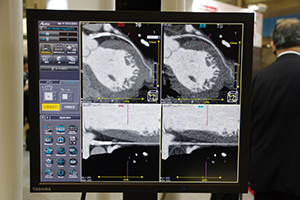

CTコーナーでは,RSNA2007で製品発表を行い,学会中の話題をさらったArea Detector CT「Aquilion ONE」の実機が国内初展示された。320列の検出器を搭載したAquilion ONEは, 1回転で脳や心臓などの臓器全体を最短で0.35秒で撮影が可能である。同社は, Aquilion 64 をはじめ,これまでCTに検出器の列数に応じた製品名をつけてきたが,今回,まったく異なる概念の新世代CTとして“Aquilion ONE”という名称がつけられた。

同装置は,連続して撮影することで四次元(三次元+時間)の情報を収集することができる。これにより,形態診断に加え,血流情報も取得することで臓器全体の動態診断が可能。脳梗塞や心筋梗塞の患者さんなど,これまで複数の診断機器で検査をする必要のあった症例の診断が1台で完了できる。関節の動きなどの動態情報も得られるため,整形外科やスポーツ医学といった領域での応用も期待されるほか,短い撮影時間で検査が終了することで,救急や小児の患者さんに対するメリットも大きい。さらに,冠動脈検査では被ばく線量を約1/4に抑えるなど,検査による被ばくを低減する。

ブースでは,呼吸下の乳児の肺や腸蠕動の様子など,多数の臨床画像を示してその有用性を紹介していたほか,320列と64列の検出器が並べて展示され,来場者の関心を集めていた。 同装置は現在,世界の14施設で稼働しており,国内では,世界で初めて導入された藤田保健衛生大学をはじめ,6施設に導入されている。